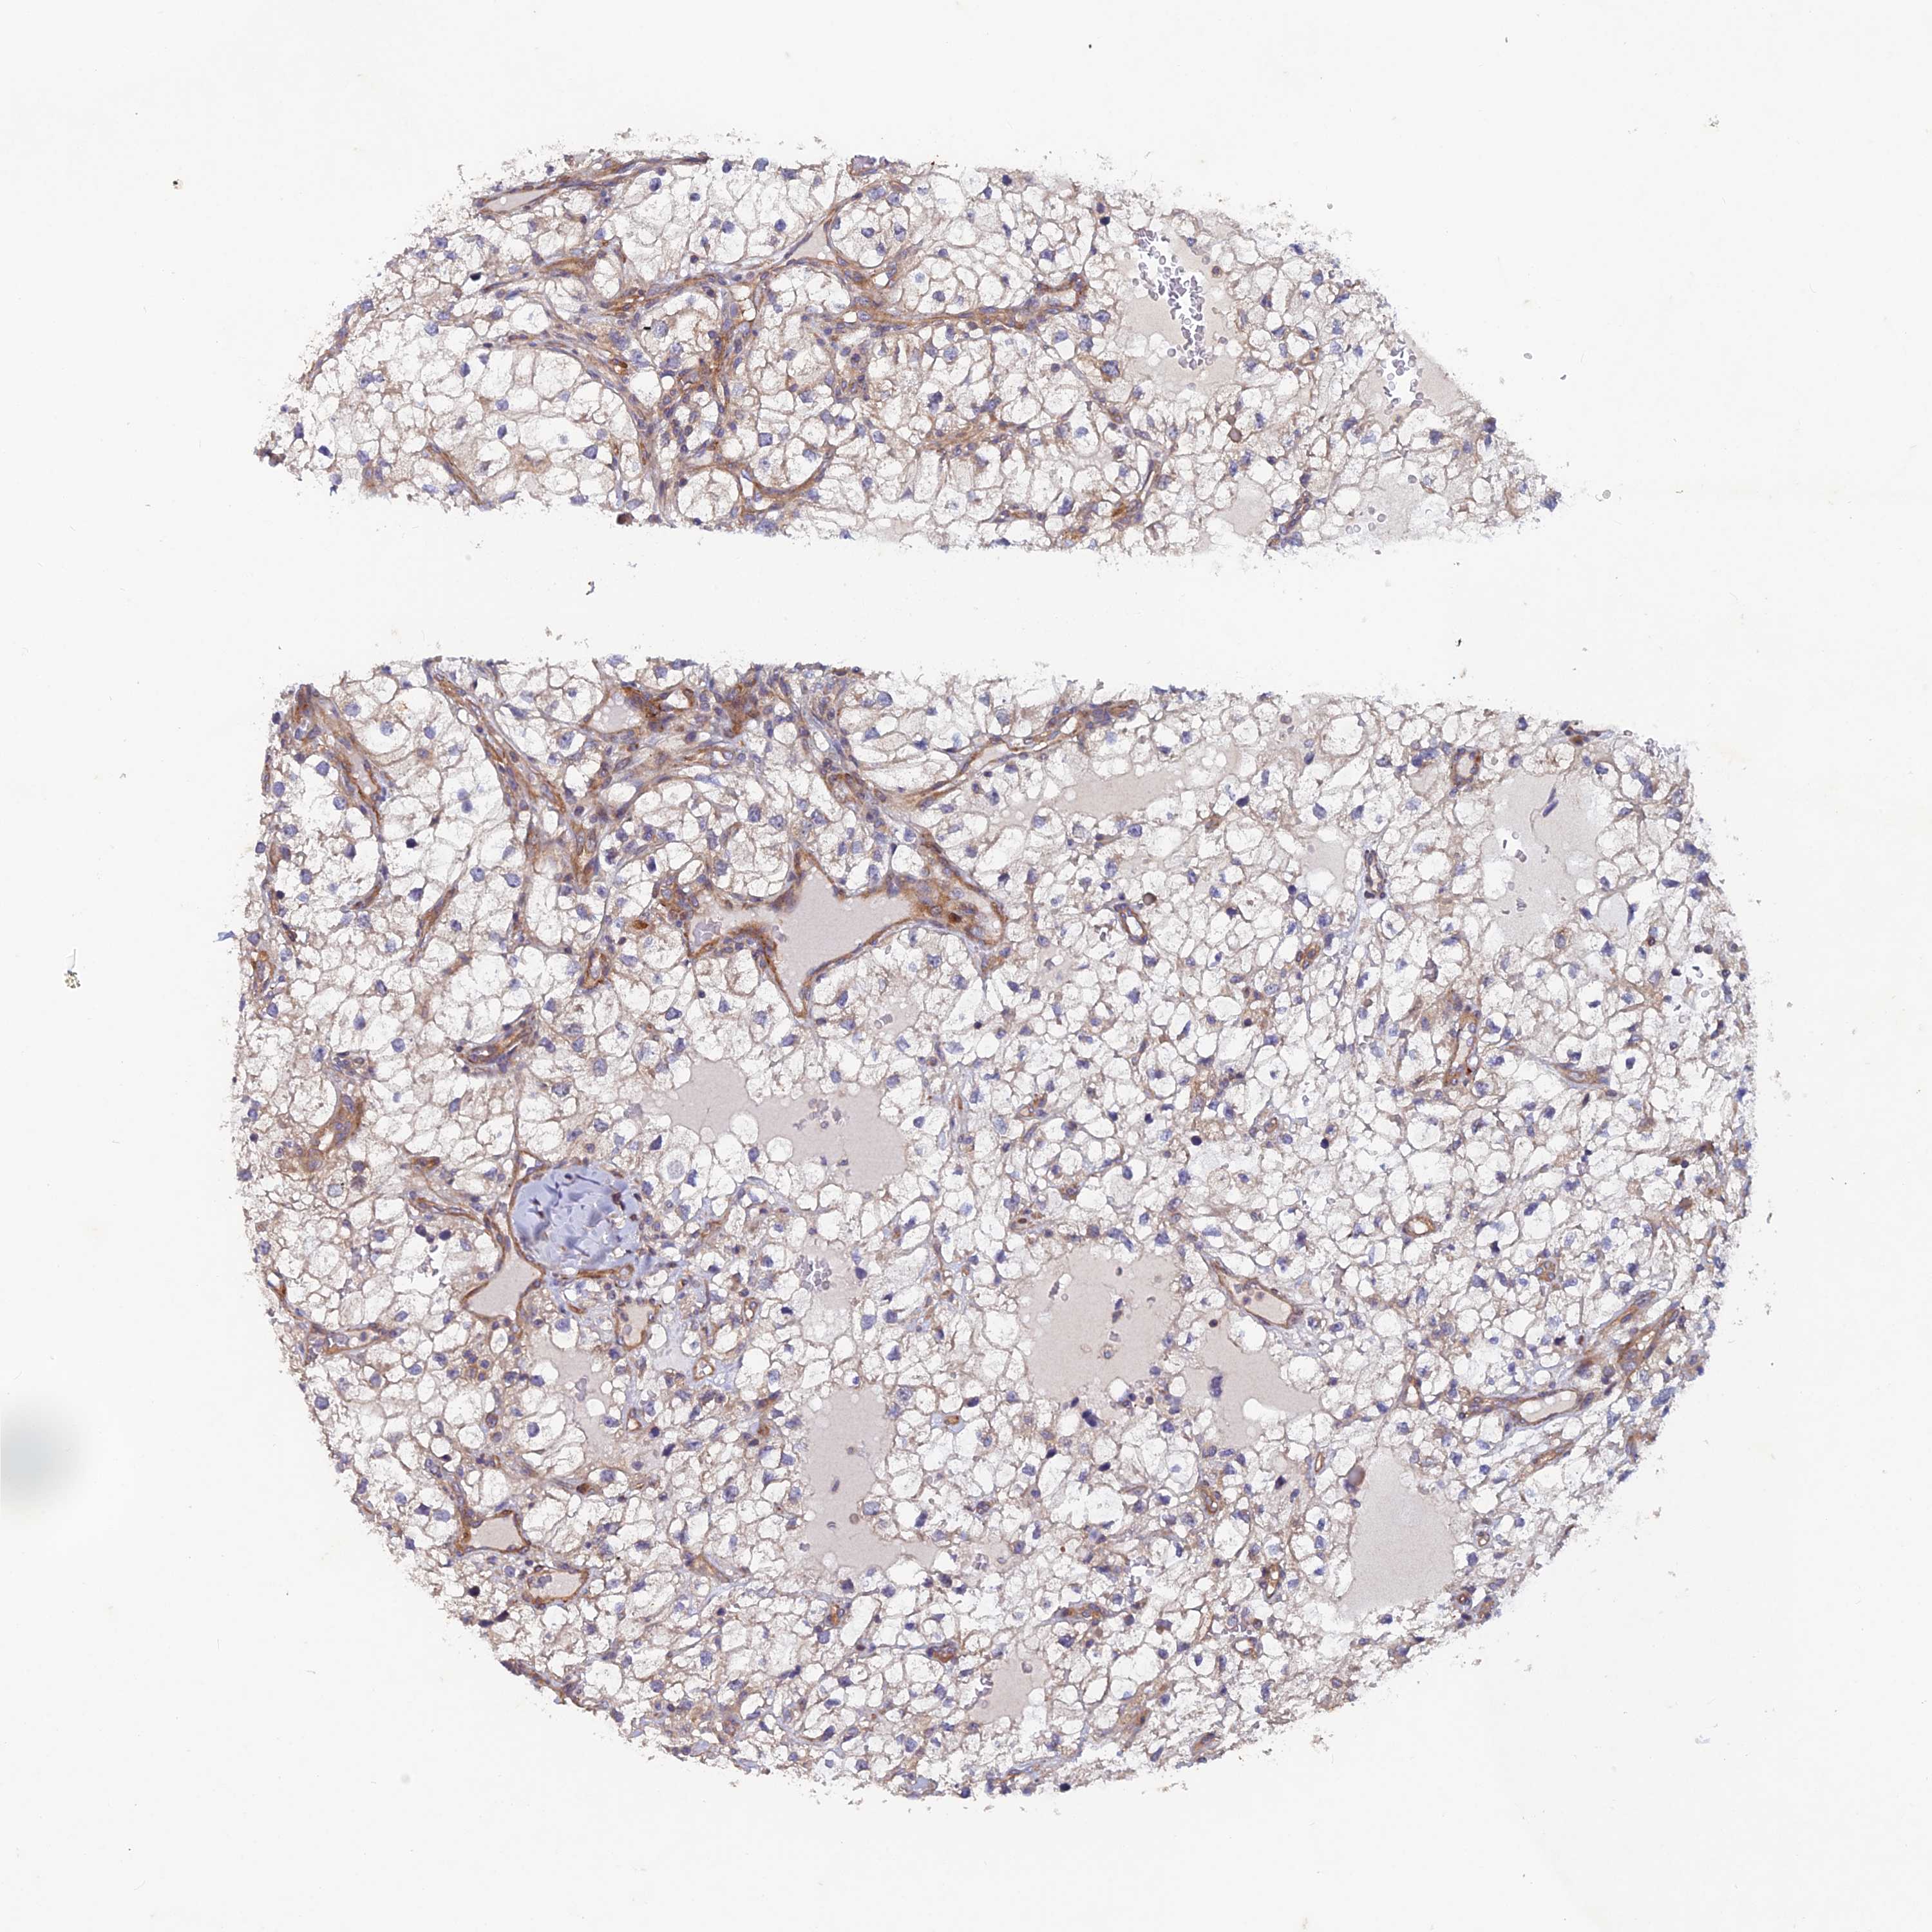

KIDNEY RENAL PAPILLARY CELL CARCINOMA (TCGA) - Interactive survival scatter ploti

The Survival Scatter plot shows the clinical status (i.e. dead or alive) for all individuals in the patient cohort, based on the same data that underlies the corresponding Kaplan-Meier plots. Patients that are alive at last time for follow-up are shown in blue and patients who have died during the study are shown in red.

The x-axis shows the expression levels (FPKM) of the investigated gene in the tumor tissue at the time of diagnosis. The y-axis shows the follow-up time after diagnosis (years). Both axes are complimented with kernel density curves demonstrating the data density over the axes. The top density plot shows the expression levels (FPKM) distribution among dead (red) and alive patients (blue). The right density plot shows the data density of the survived years of dead patients with high and low expression levels respectively, stratified using the cutoff indicated by the vertical dashed line through the Survival Scatter plot. This cutoff is automatically defined based on the FPKM cutoff that minimizes the p-score. The cutoff can be changed by dragging the vertical line or by entering a cutoff value in the square labeled "Current cut-off".

Under the Survival Scatter plot the p-score landscape (black curve; left axis) is shown together with dead median separation (red curve; right axis). Dead median separation is the difference in median mRNA expression between patients who have died with high and low expression, respectively. It is calculated as follows: median FPKM expression of dead patients with high expression - median FPKM expression of dead patients with low expression. This is intended to aid the user in visually exploring custom cutoffs and the associated p-scores and dead median separation.

Individual patient data is displayed and can be filtered by clicking on one or more of the category buttons on the top of the page. Categories describing expression level and patient information include: high, low, alive, dead, female, male and tumor stages. The scale of the x-axis can be toggled between linear and log-scale by clicking on the "x log" button. Mouse-over function shows TCGA ID, patient information and mRNA expression (FPKM) for each patient.

& Survival analysisi

Kaplan-Meier plots summarize results from analysis of correlation between mRNA expression level and patient survival. Patients were divided based on level of expression into one of the two groups "low" (under cut off) or "high" (over cut off). X-axis shows time for survival (years) and y-axis shows the probability of survival, where 1.0 corresponds to 100 percent.

NCAPG is not prognostic in Kidney Renal Papillary Cell Carcinoma (TCGA)

Best expression cut offi

Based on the FPKM value of each gene, patients were classified into two groups and association between prognosis (survival) and gene expression (FPKM) was examined. The best expression cut-off refers the FPKM value that yields maximal difference with regard to survival between the two groups at the lowest log-rank P-value. Best expression cut-off was selected based on survival analysis .

When clicking on this number, the vertical dashed line indicating cut-off, the interactive survival plot, and the Kaplan-Meier curve will be adjusted to show results based on the best expression cut-off.

: N/A